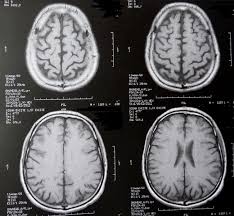

Hirnmetastase Wikipedia